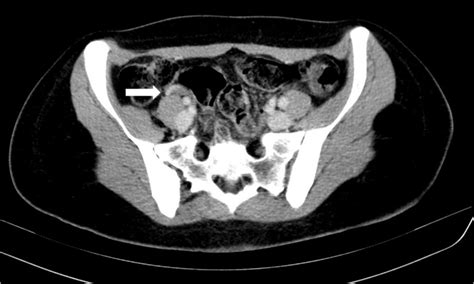

Imaging studies are crucial for diagnosing septic pelvic thrombophlebitis. Commonly used imaging modalities include:

• Computed tomography (CT) scan with contrast to visualize the pelvic veins and detect the presence of blood clots.

Case Study 1: A 32-year-old woman presented with fever, abdominal pain, and pelvic tenderness two weeks after a cesarean section. She had a history of endometritis and was diagnosed with septic pelvic thrombophlebitis based on a CT scan. She was treated with broad-spectrum antibiotics and heparin, and her symptoms resolved within a week.

Case Study 3: A 28-year-old woman presented with severe pelvic pain and fever three days after a hysterectomy. She was diagnosed with septic pelvic thrombophlebitis based on a CT scan and blood cultures. She underwent surgical drainage of an abscess and was treated with antibiotics and heparin. Her symptoms resolved, and she was discharged after a week.